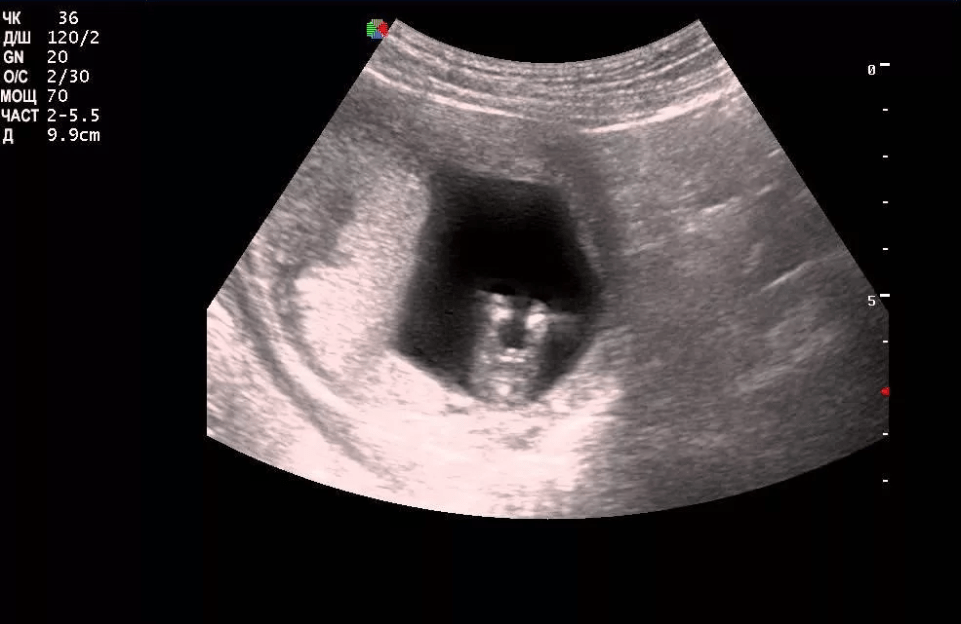

На этом сроке УЗИ делают, чтобы подтвердить беременность и определить, развивается она в матке или вне ее. Даже самый лучший врач не сможет определить пол малыша: хотя половые бугорки, из которых потом разовьются наружные половые органы, уже есть, но они слишком малы, чтобы уверенно разглядеть их.

На 6-й неделе весь малыш имеет размер всего 3,5 мм, на 7-й – 5-7 мм, на 8-й, после резкого скачка роста, аж 2,5 см, но микроскопические половые бугорки видны плохо, да и выглядят пока одинаково у мальчиков и девочек.